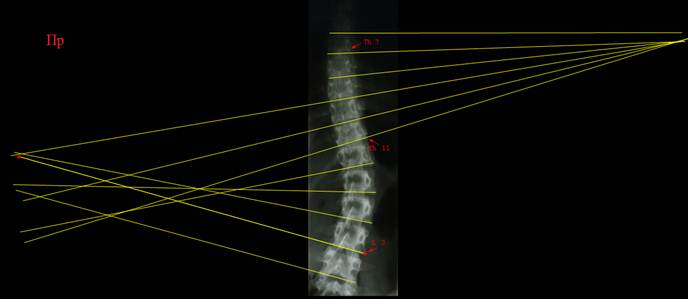

Прямая

рентгенограмма позвоночника ребенка 14 лет, сколиотическая деформация в грудном

и поясничном отделе компенсированная, S –

образная, выражена ротация позвонков. На

первом рисунке выполнен поиск нейтральных позвонков при помощи линий. На

практике так не делают, множество линий мы провели для наглядности примера.

Красными стрелками обозначены позвонки, линии которых дали максимальный угол

при пересечении. Вы видите, что найти эти позвонки будет не так уж трудно и без

множества линий. На следующем рисунке лишние линии убраны и проведены

перпендикуляры к линиям нейтральных позвонков. Красными стрелками обозначены

углы дуг (углы по Коббу). Угол основной дуги составил 30°, компенсаторной

- 14°. Деформация достаточно серьезная, это третья степень.